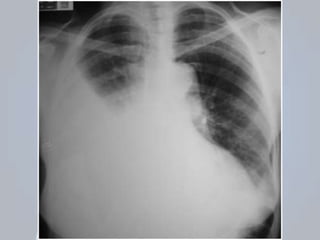

HEMOTÓRAX

 Presença de sangue no espaço pleural;

 Representa fonte de perda sanguínea importante;

 Mesmos mecanismos do pneumotórax;

 Origem: parede da musculatura torácica, vasos

intercostais, parênquima pulmonar, vasos

pulmonares ou grandes vasos do tórax;

 AVALIAÇÃO: desconforto; dor torácica e a dispneia;

Sinais de choque: taquicardia, taquipneia, confusão,

palidez e hipotensão.

 EXAME FÍSICO: sons respiratórios são diminuídos

ou ausentes; percussão é abafada;

 PNEUMOTÓRAX + HEMOTÓRAX: probabilidade de

comprometimento cardiorrespiratório;